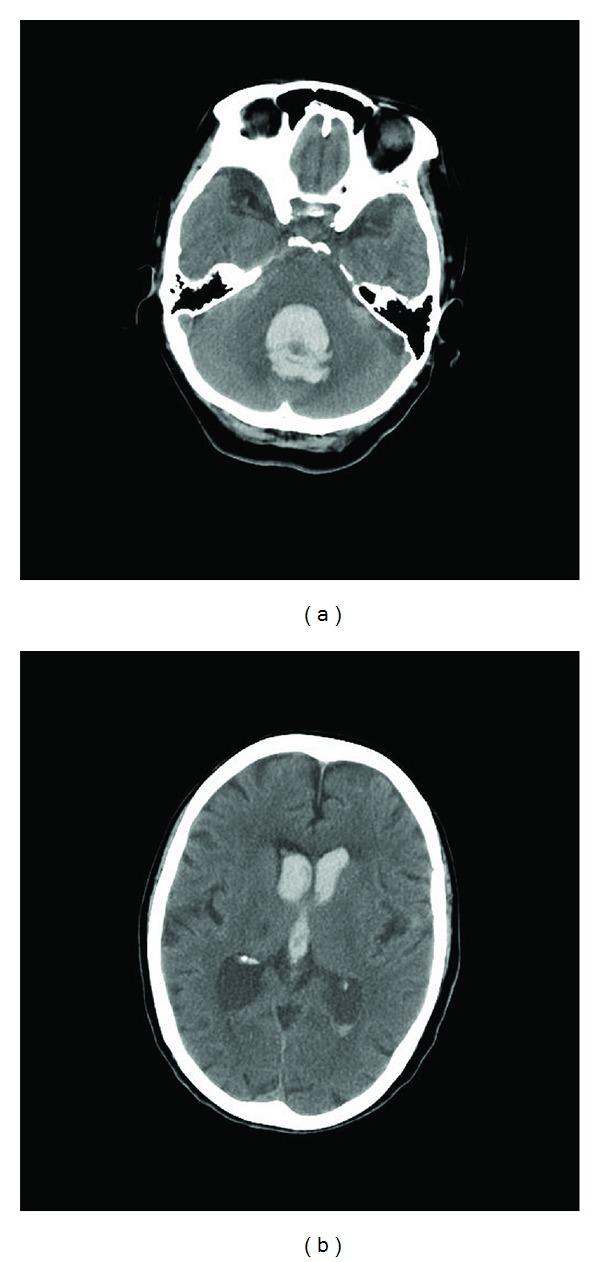

We report a 71-year-old woman with takotsubo-like myocardial dysfunction accompanied with cerebellar hemorrhage. On admission time, although she was unconscious by cerebellar hemorrhage, no obvious heart failure and serological disorder were observed. Three days later, operation for extraventricular drainage was performed. However, conscious level did not change. Four days after admission, the change of electrocardiogram wave pattern and the decrement of heart wall motion were detected. These findings revealed takotsubo-like myocardial dysfunction had occurred. Physical stresses by cerebellar hemorrhage and cranial operation might cause cardiac disorder. This is a remarkable case of takotsubo-like myocardial dysfunction, which is brought about cerebellar hemorrhage against subarachnoid hemorrhage.

我们报告了一名71岁女性,患有类似应激性心肌病的心肌功能障碍并伴有小脑出血。入院时,尽管她因小脑出血而昏迷,但未观察到明显的心力衰竭和血清学紊乱。三天后,进行了脑室外引流手术。然而,意识水平并未改变。入院四天后,检测到心电图波形变化和心壁运动减弱。这些发现表明发生了类似应激性心肌病的心肌功能障碍。小脑出血和开颅手术引起的身体应激可能导致心脏疾病。这是一例由小脑出血而非蛛网膜下腔出血引发的类似应激性心肌病的显著病例。